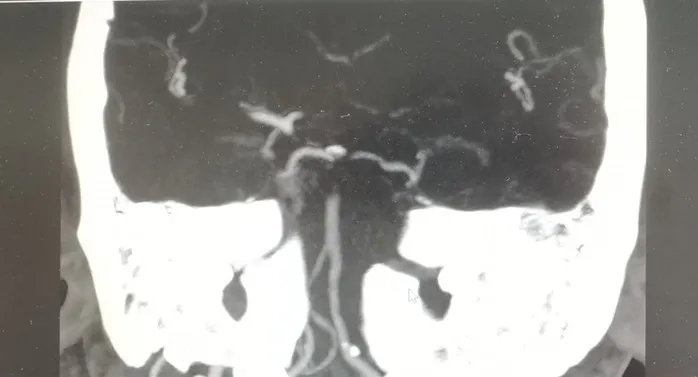

接診的神經(jīng)內(nèi)科周平醫(yī)師快速評估病情后高度懷疑腦血管意外的可能,急診行頭、胸部CT示:急性腦梗死,溶栓刻不容緩!在家屬知情同意后,立即為徐大爺開通綠色通道,阿替普酶(rt-PA)靜脈溶栓治療爭分奪秒地開始了(DNT時(shí)間27分鐘),同時(shí),考慮到患者可能為后循環(huán)大血管的堵塞,在靜脈溶栓的同時(shí)行頭、頸CTA檢查,結(jié)果示基底動(dòng)脈中上段閉塞。

CTA影像